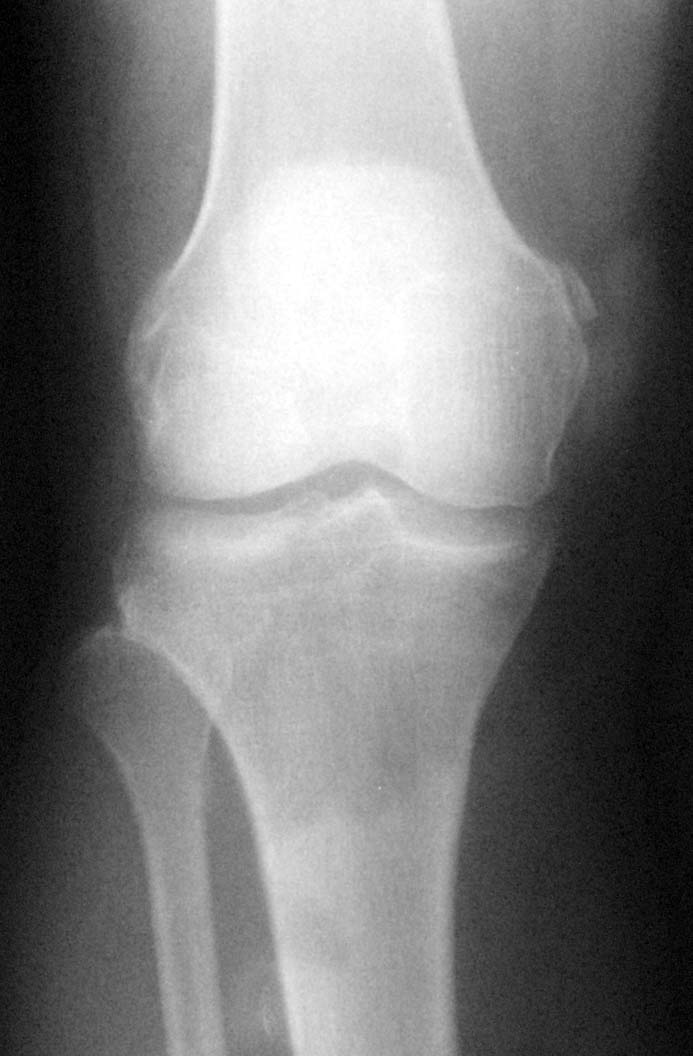

膝关节外伤,请看股骨内上髁外方是否为骨折?

支持楼主意见(撕脱性骨折)。

除了股骨外髁撕脱骨折外腓骨小头是否有骨折。

撕脱骨折。

应该是撕脱骨折。

撕脱骨折

支持撕脱骨折诊断,肌腱钙化不排除.

楼主说的外上髁,骨质未见明显异常;而内上髁有撕脱骨折.

股骨外上髁没发现异常,内上髁示斑片状骨质密度影,建议结合临床,透视旋转体位确定病人疼痛部位,撕裂骨折应该有固定疼痛。

支持撕脱骨折.高密度影内缘模糊,不象软组织的钙化,而且股骨内髁局部软组织肿胀明显.

不考虑骨折,因为结合正侧位片均未见主骨干上有与其等大之低密度区,所以本人考虑股内侧肌肌腱附着点钙化。

还是考虑撕脱性骨折为好,因为这个病人是因为外伤来的,并且与骨皮质不连续。

局限性骨化性肌炎>撕脱骨折,检查一下病人,局部的压痛是否明显

内上髁周围软组织肿胀,可考虑撕脱骨折,

不考虑骨折,因为我已发现两例,压痛点均不在此处,结合正侧位片均未见主骨干上有与其等大之低密度区,所以本人考虑股内侧肌肌腱附着点钙化。但愿能得到更好的证实!

不支持骨折。

支持钙化。

理由---1、边缘光滑锐利。2、相邻股骨无缺损。

为慎重起见1、检查此处有无压痛、外伤是否在此处。2、加照斜位。3、随诊复查。